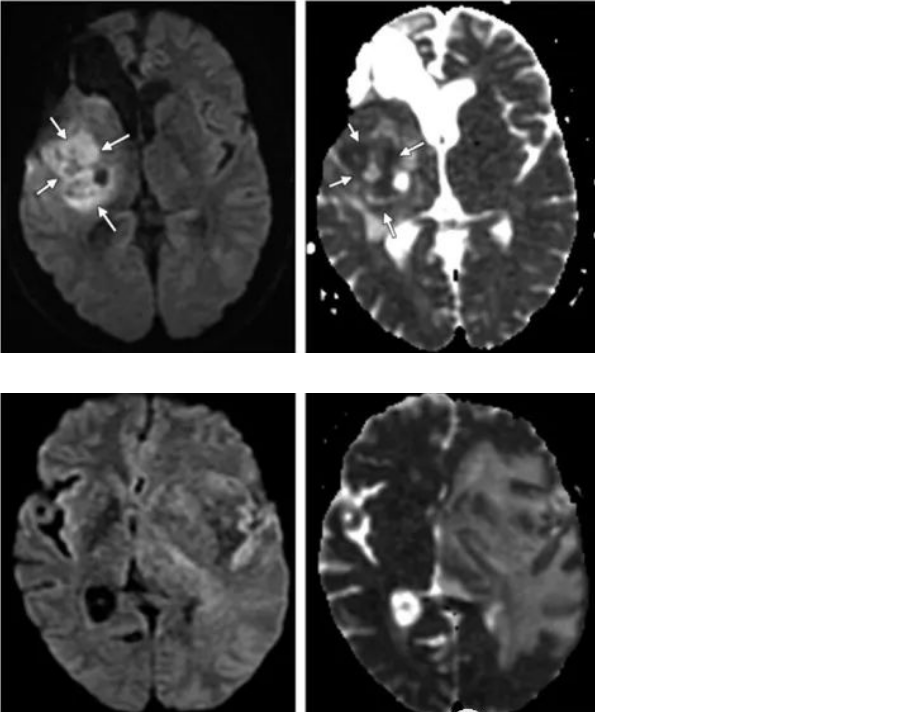

2.DWI弥散加权成像

+放射性脑损伤:细胞液化坏死,细胞外间隙水分子增多,弥散增加。